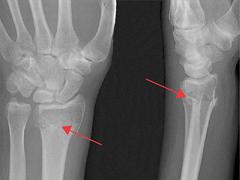

De distale radiusfractuur is een veelvoorkomende fractuur die meestal ontstaat door een val op de uitgestrekte hand. Voor dit type fractuur worden verschillende classificatiesystemen gebruikt, maar in de literatuur is geen consensus over welk systeem gebruikt dient te worden. Op basis van de ernst van de fractuur en patiëntkarakteristieken zal de behandelend arts kiezen voor een conservatieve dan wel operatieve behandeling. Het is van groot belang dat de patiënt al vroeg in het revalidatietraject goed wordt begeleid door een fysiotherapeut. De revalidatie is in te delen in verschillende fasen: in eerste instantie ligt het accent op het verbeteren van de mobiliteit, in een latere fase steeds meer op het opbouwen van de belastbaarheid. Tijdens de nabehandeling is het belangrijk om eventuele complicaties te herkennen, zodat hiervoor een gerichte interventie kan worden toegepast.